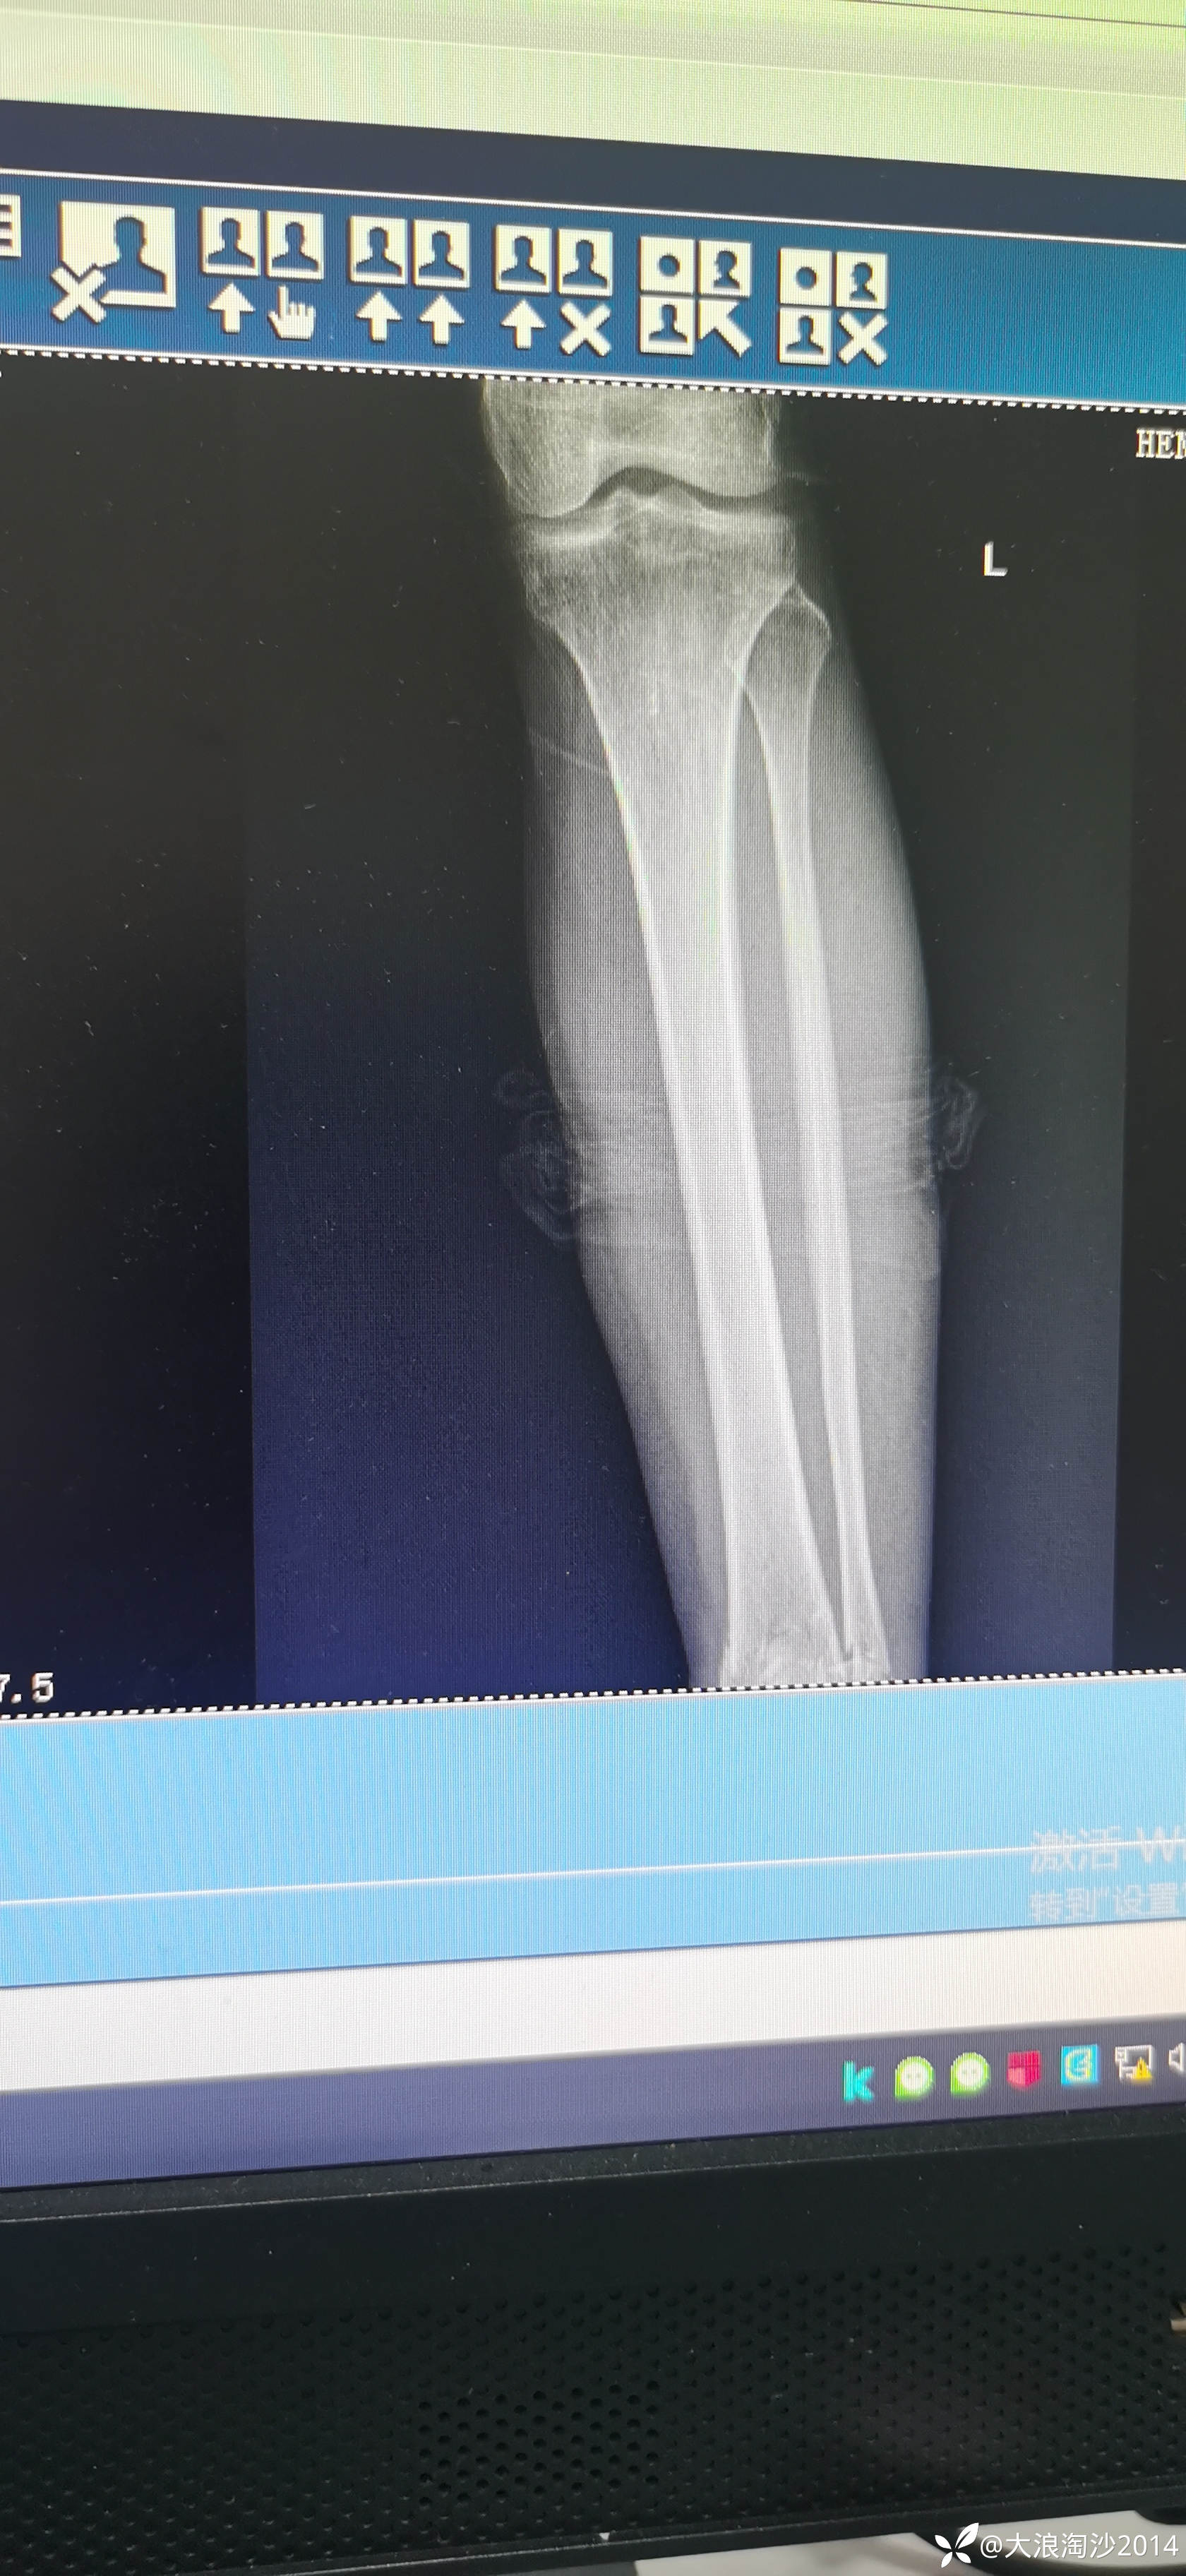

一65岁女性患者,偏瘦,体重75斤,车祸外伤致左胫腓骨远端骨折,入院后消肿后,病人可以用皮包骨头形容,考虑胫骨远折端不适合用内侧插板(mippo技术),病人太瘦,如取两个切口分别处理胫腓骨,切口容易出现问题,因此采用前外侧一个切口处理胫腓骨远端骨折(片子顺序上传有点乱)